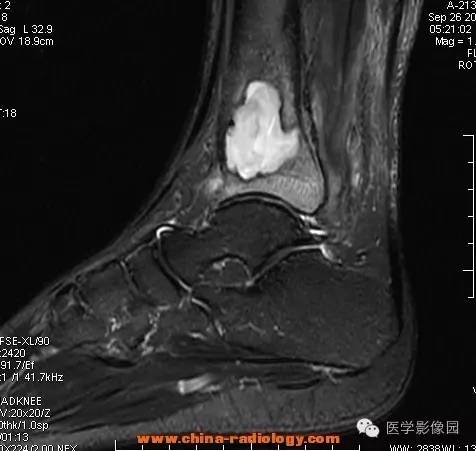

影像学表现:胫骨中下段干骺端不未规则形长T1长T2信号,T2WI见不完整环形稍低信号影,T2脂肪抑制低信号更明显,并见胫骨下段及踝关节后外侧软组织呈弥漫稍高信号,增强明显不均匀强化,增强见低信号环内有环形强化影。

影像学表现:表现为长骨干骺端有椭圆形密度减低区,边缘有清晰的骨质硬化,病变与邻近正常骨髓腔境界清楚。MRI上T1WI呈低信号,少数呈等信号,T2WI多为混杂高信号,增强扫描可见环状强化,强化的脓肿壁薄而均匀。